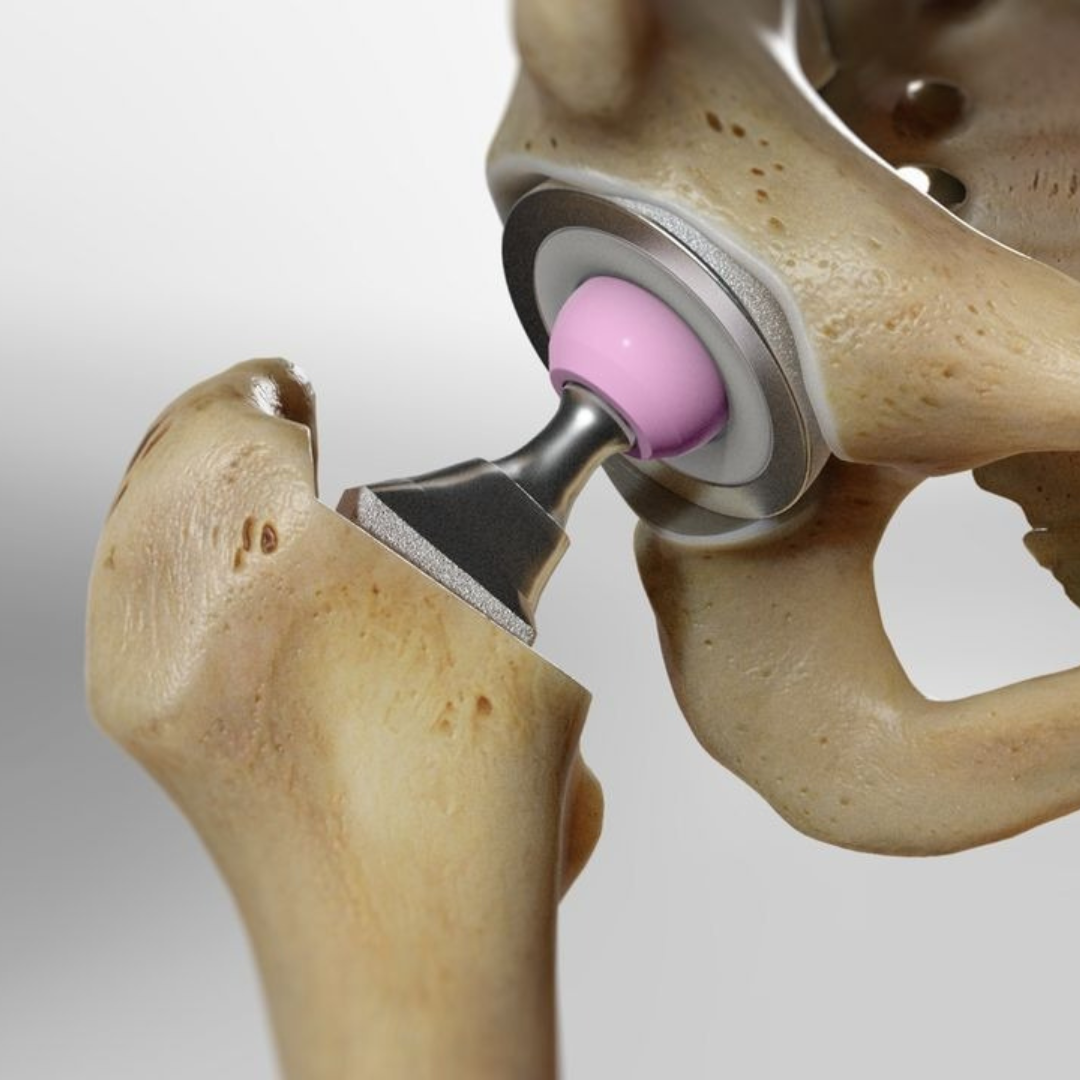

HIP REPLACEMENT

Hip replacement is a surgical process to replace the damaged bone and cartilage with prosthetic components. Jyraj Clinic is the leading multi-specialty clinic having immense experience in performing hip replacement surgeries.